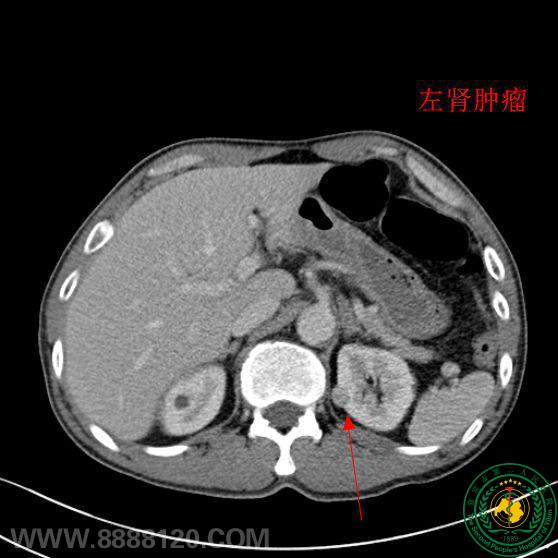

“迎难而上,造福患者”,宜宾市第二人民医院泌尿外科顺利完成一例高难度肾部份切除术

“迎难而上,造福患者”,宜宾市第二人民医院泌尿外科顺利完成一例高难度肾部份切除术28404